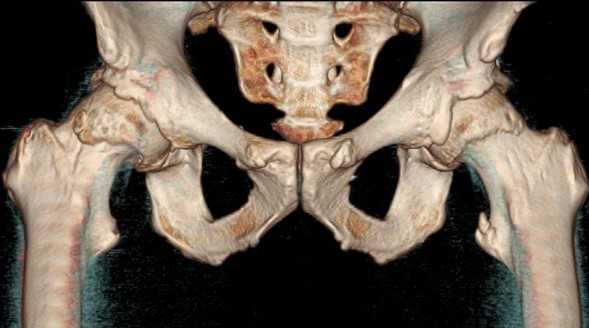

![Трехмерная реконструкция тазобедренных сочленений]()

Трехмерная реконструкция тазобедренных сочленений

КТ тазобедренного сустава

КТ тазобедренного сустава используют для дифференциальной диагностики заболеваний, установления причины и характера патологического процесса.